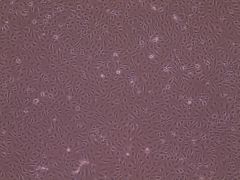

SNU-182人肝癌细?2018年新引进)

T24人膀胱移行细胞癌细胞(2013年新引进)

HT-1080人纤维肉瘣/a>

HEK-293A人胚肾细胝/a>

PIEC猪髋动脉内皮细胞

Calu-6人退行性癌细胞

F56人腺癌细胝/a>

VSC4.1大鼠脊髓前角运动神经元瘤细胞

hCMEC/D3人脑血管上皮样细胞

HAL-01人淋巴细胞白血病细胝/a>